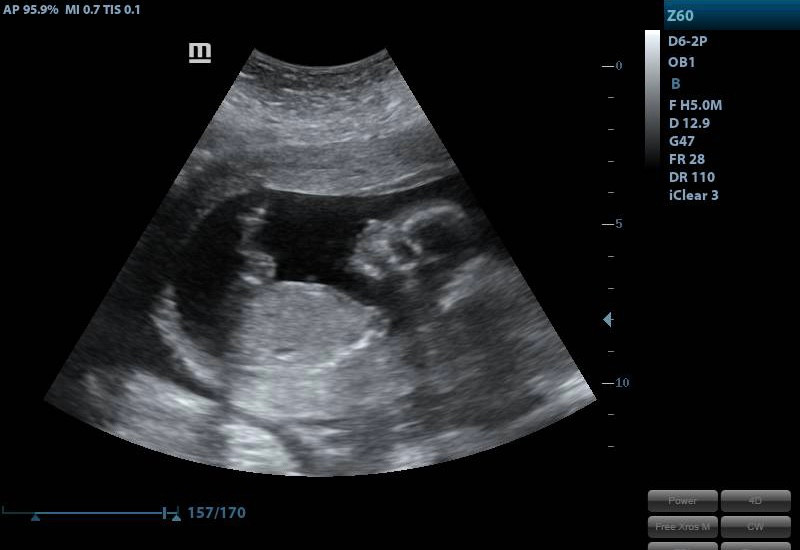

My business is a mobile ultrasound company. I come to your home, bring everything I need and do your Ultrasound while you lay on your couch surrounded by friends and family. I have had so much fun getting to know my families and doing all the fun parts of ultrasound. I do early pregnancy, gender reveals, baby showers, 2D and 3D/4D. Getting started wasn’t easy, I built my website, I got an equipment loan, I got some quotes, purchased my equipment and started advertising my services with social media.